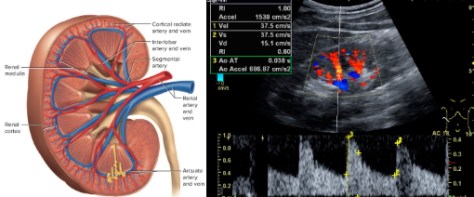

УЗД нирок, наднирників, ниркових артерій (для обстеження при артеріальній гіпертонії):

УЗД нирок, наднирників, з кольоровим та спектральним доплерівським дослідженням ниркових артерій та кровоплину в нирках (з метою виявлення хронічних захворювань нирок, стеноза судин нирок, пухлин наднирників).